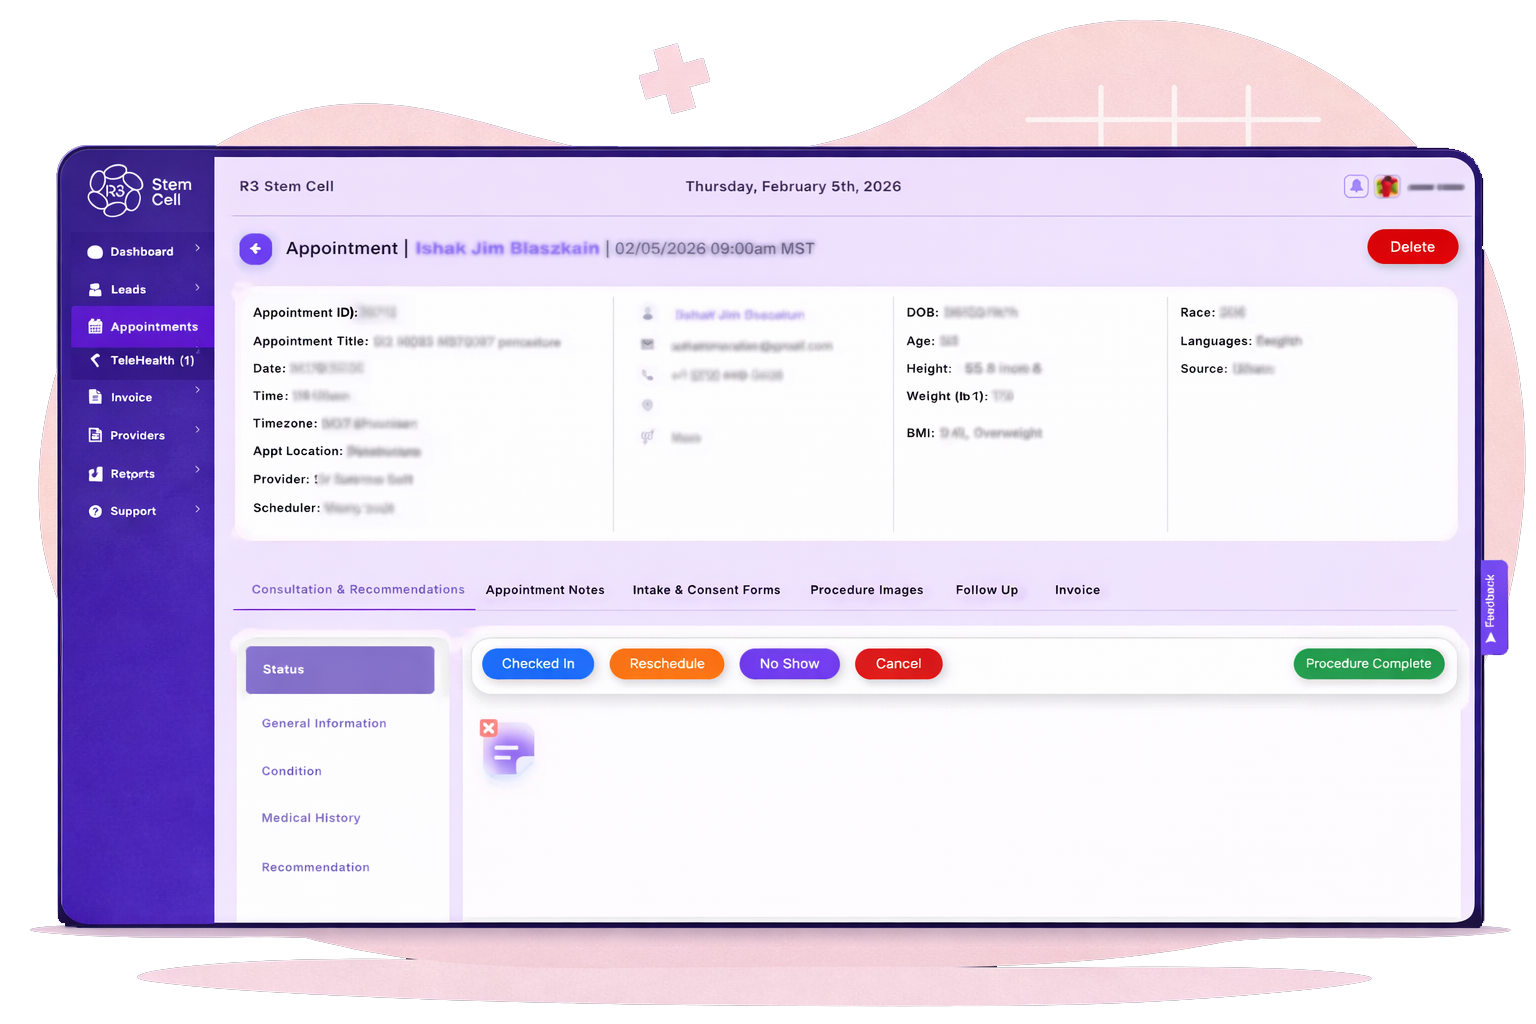

Appointment Scheduling

Built for rotating providers and multiple locations. Cancellations reopen availability instantly.

Appointment Scheduling

Scheduling breaks down when providers rotate between locations. PracticeHalo accounts for that.

Example: Dr. Patel works Tuesdays in Atlanta and Thursdays in Savannah. Patients only see valid time slots. Cancellations reopen availability instantly. No manual updates. Reporting highlights patterns in cancellations, no shows, and provider availability.

Patient & Clinical Management

Patient and Clinical Management

PracticeHalo keeps complete patient records in one place:

Contact details and demographics

Visit history and treatment notes

Communication logs

Appointments

Invoices and payments

Staff can pull up any patient file in seconds. When a patient calls about their last service or remaining balance, the front desk has everything on one screen—answers delivered in under 30 seconds. No transfers. No callbacks.

Because everything is connected, your team spends less time chasing information and more time helping patients—reducing administrative workload while delivering a smoother, more professional experience.